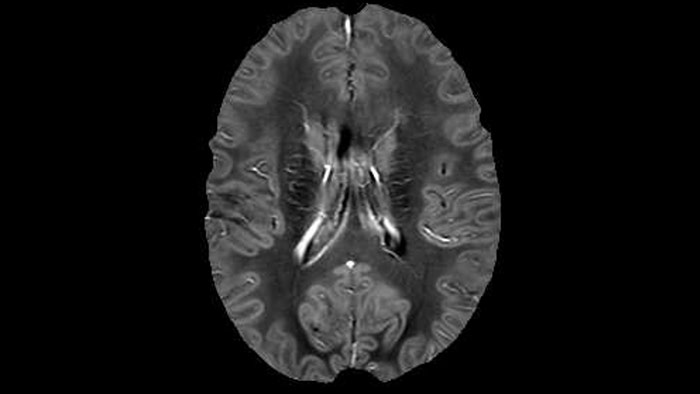

QSM based on a Compressed SENSE multi-echo SWI.

Dr. Rauscher says, “With better gradients we can use a shorter echo spacing on the spin echo, so we get better sampling of the rapidly decaying myelin signal, which typically has T2 of around 10-20 milliseconds at 3 Tesla. If we can reduce echo spacing from about 8 to 5-6 milliseconds, we get a much better sampling of the short decay component and increase our SNR, which is a big advantage. The same is true for multi-echo gradient echo which we use for susceptibility mapping and for mapping venous vessels in MS.”

He says the accelerated scanning is achieved via the use of Compressed SENSE and MultiBand SENSE. “We can use Compressed SENSE acceleration factors of about 10 on a 3D FLAIR for instance, which is quite remarkable compared with what we saw with the Achieva. With 3D FLAIR, we can push the spatial resolution to 0.3 cubic mm and it works. Previously, our 3D FLAIR scans lasted about 8 minutes, but now with Elition they are five minutes. The SNR is also visibly better. Our SWI and QSM scans look fantastic. Also, since a lot of neuroimaging is EPI based, using the MultiBand SENSE technique can increase temporal resolution and make it possible to run complicated DTI scans relatively quickly.”